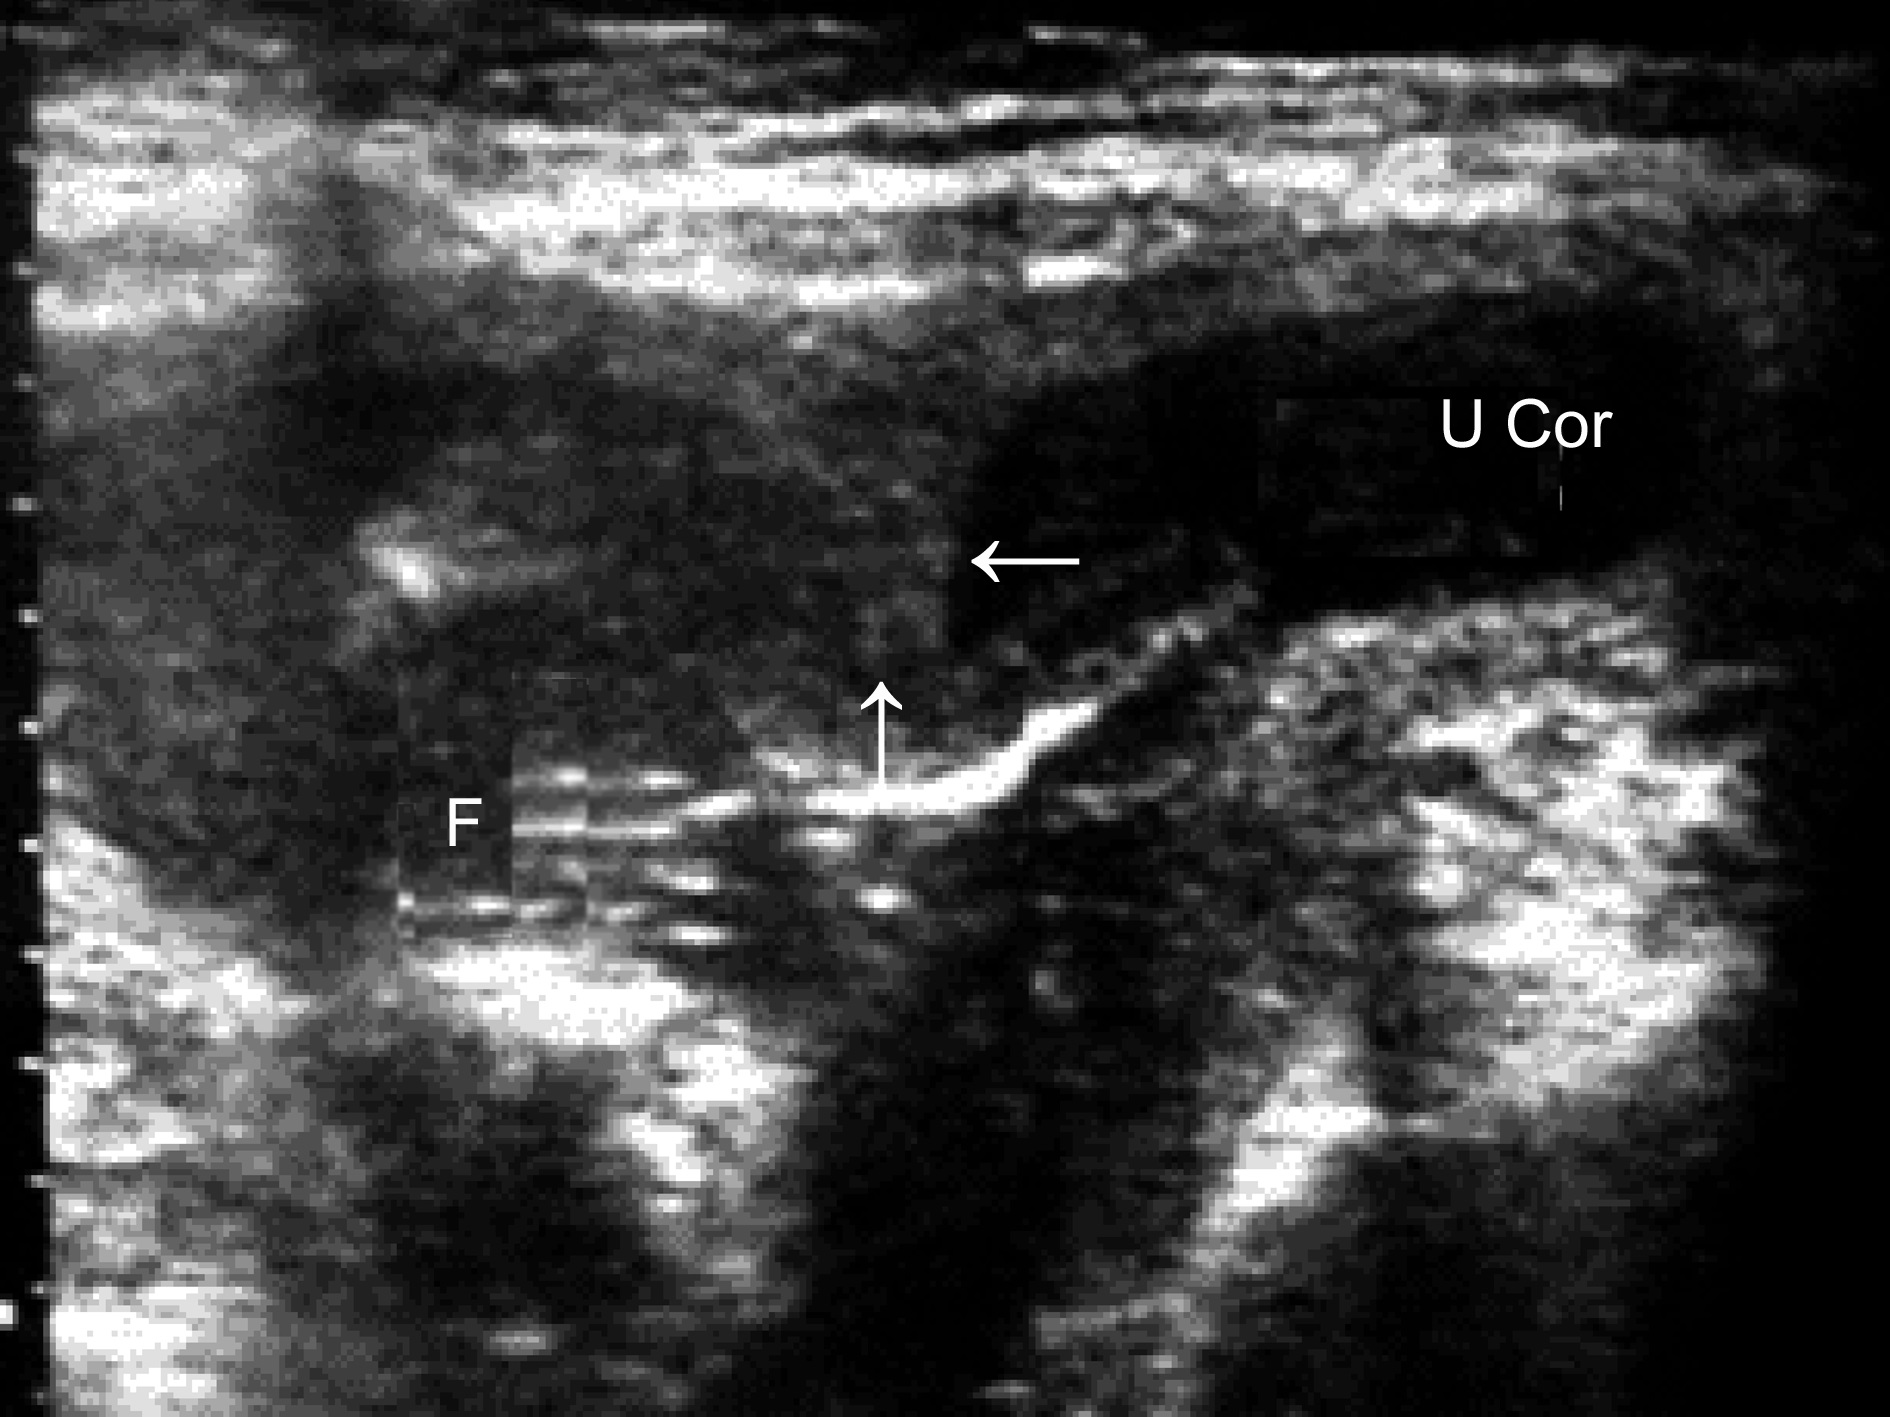

双角子宫是一种相对常见的子宫先天性发育异常,由双侧副中肾管融合不完全而形成。在典型的情况下,超声显象检查可以显示子宫底部呈马鞍形,两侧角部向左右外上方延伸、突出(图1);受精卵种植常偏向一侧或在偏下的子宫腔内;双角子宫并不乏双胎妊娠的报告。超声显象检查可以准确地显示妊娠囊的位置。中期妊娠后超声检查可显示双角子宫之一突出的角部形成的较阔的羊水池,但总体衡量并无羊水过多的征像。

图1双角子宫妊娠:宫底外缘凹陷,内缘向宫腔内突出(箭头),右侧宫腔见胎体(F),左侧角部(U Cor)突出

双角子宫妊娠时可由于羊膜腔形态的异常引起胎位异常,或由于子宫肌壁的异常引起子宫收缩乏力。